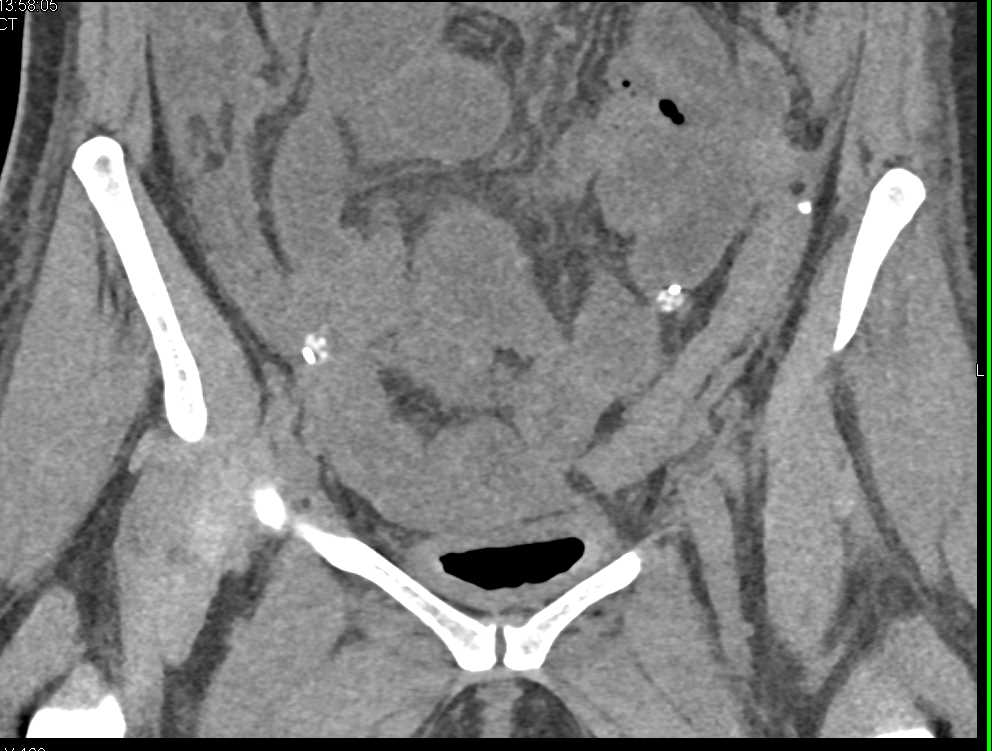

Extravasation from the Bladder